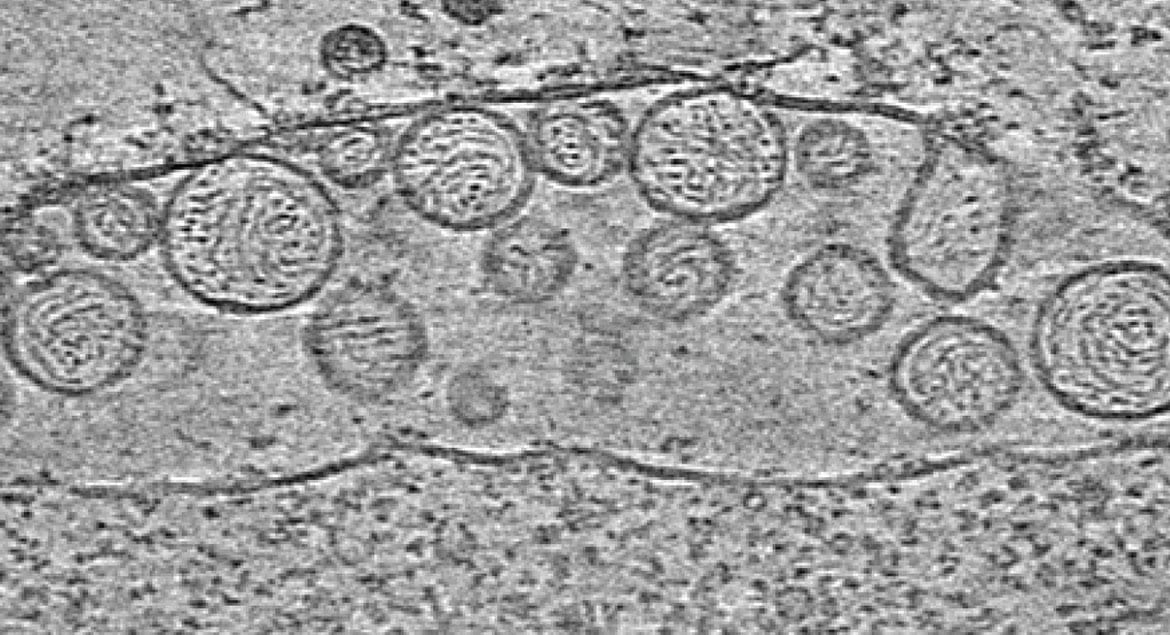

Криоэлектронная микроскопия митохондрии, содержащей РНК-вирионы. Иллюстрация: morgridge.org.